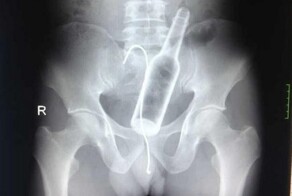

Мальчик четыре дня страдал от боли, прежде чем обратиться за медицинской помощью. Позже он признался, что около недели назад проглотил 80-100 неодимовых магнитов. Он рассказал врачам, что купил их в зарубежном интернет-магазине Temu. Рентген показал, что магниты, запрещённые в Новой Зеландии с 2013 года, образовали «четыре линейные цепочки» в кишечнике.

Врачи, подготовившие отчёт, — Бинура Лекамалаге, Люсинда Дункан-Вере и Никола Дэвис — отметили: «В ходе операции были обнаружены несколько цепочек магнитов в тонком кишечнике и слепой кишке. Они соединились в правом нижнем квадранте, сдавив ткани и вызвав некроз».

Длительное воздействие магнитов нарушило кровоток и снабжение тканей кислородом, что привело к их гибели.